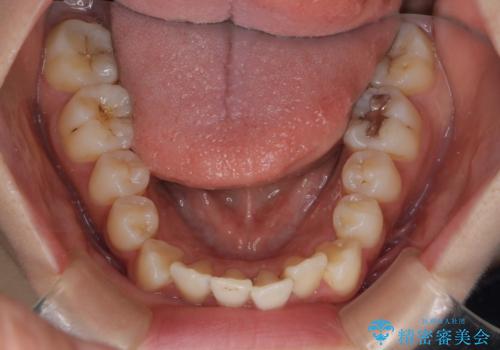

【インビザライン】マウスピースで開咬改善

- 開咬を主訴に来院されました。

IPR(歯と歯の間を削る処置)と顎間ゴムを行いながら、インビザラインで開咬を治療する計画を立てました。

治療をしながら、MFT(口腔筋機能療法)も行っていくことにしました。